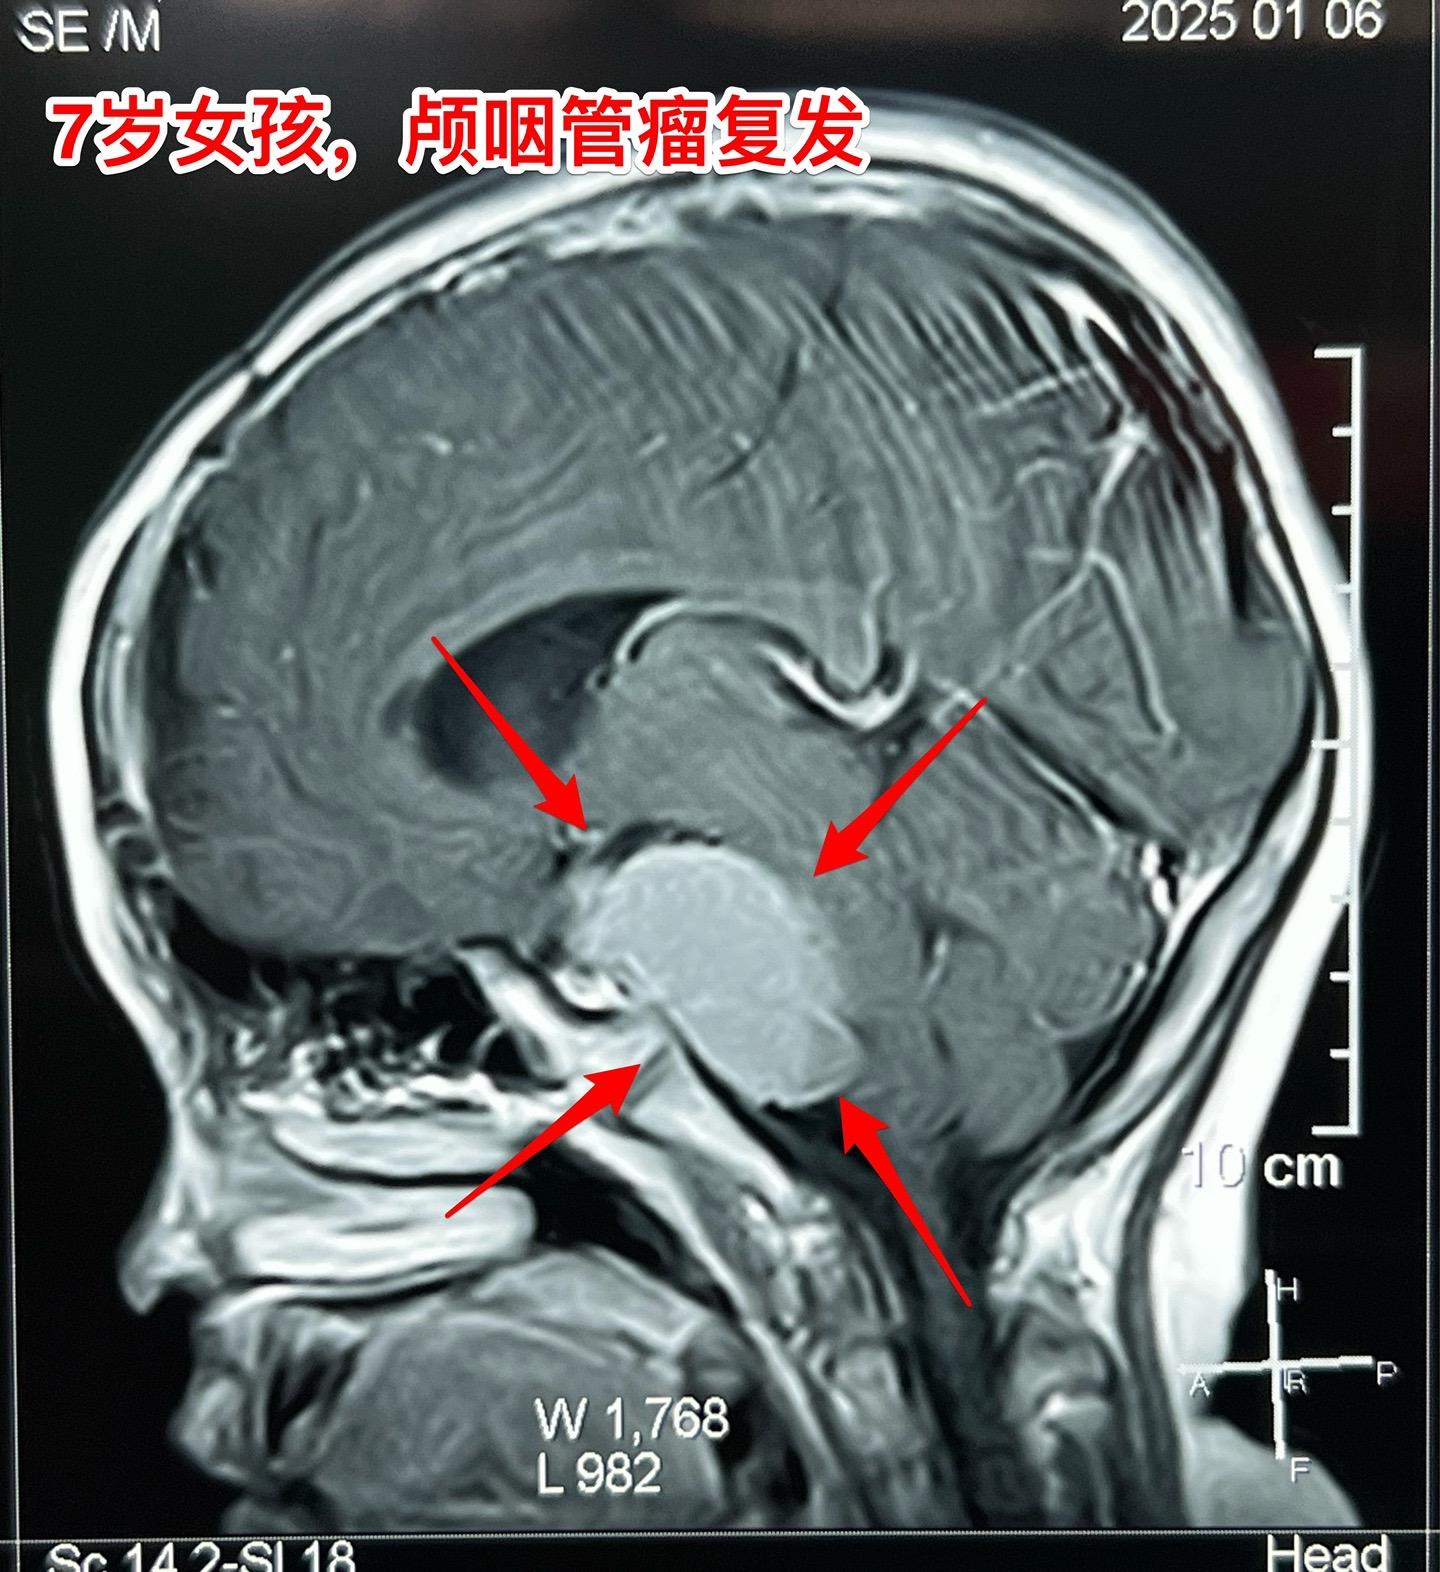

颅咽管瘤复发,看起来是一个瘤其实有三个。7岁女孩子,颅咽管瘤复发。从CT和磁共振来看,是一个大的囊性肿瘤,体积很大了,肿瘤向后颅窝生长,手术切除的难度还是比较大的。 2025年1月10日作手术过程中发现的情况比预想的还要复杂得多。除了这个大的囊性肿瘤之外还发现了两个孤立肿瘤。 这样的情况在我们科并不罕见,经常发现复发的颅咽管瘤病人脑部不止是一个瘤,有的时候有超过10个孤立的肿瘤。这种情况就要考验医生的技术和意志力了。当然,在我们科,总是争取把看见的瘤完全切除。